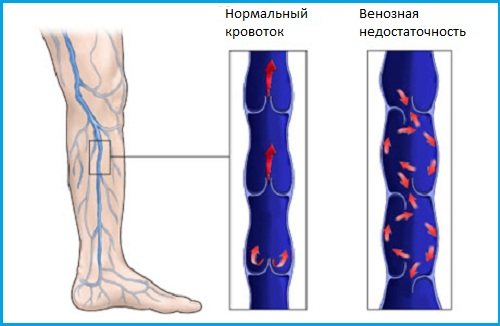

Хроническая венозная недостаточность

Под венозной недостаточностью понимают комплекс клинических проявлений, возникающих вследствие нарушения кровотока в венах. Они могут беспокоить при варикозном расширении вен, венозных аномалиях, посттромботической болезни. К основным симптомам ХВН относят:

- ощущение распирания в икрах;

- тянущие боли под коленом сзади;

- жжение в ступнях;

- дискомфорт в задней или передней поверхности голени.

При развитии патологии человеку хочется опустить ноги в холодную воду, поднять их вверх, полежать, забросив конечности на стену. Неприятное чувство обычно возникает к вечеру и практически не проявляется в утренние часы. Нередко боль сопровождается отечностью, а на кожных покровах образуются сосудистые звездочки или проступает венозная сетка. При подобных признаках рекомендуется посетить флеболога.

- Венозный застой нижних конечностей хорошо устраняется с помощью применения местных мазей для предупреждения образования сгустков крови и купирования воспаления. Обычно это «Гепарин» или «Троксевазин». Одновременно требуется ношение компрессионного белья. Запущенные формы варикоза устраняют с помощью хирургического вмешательства. Нередко используются малоинвазивные методы с введением склерозирующего вещества в поврежденный сосуд с отключением его от системы кровообращения.